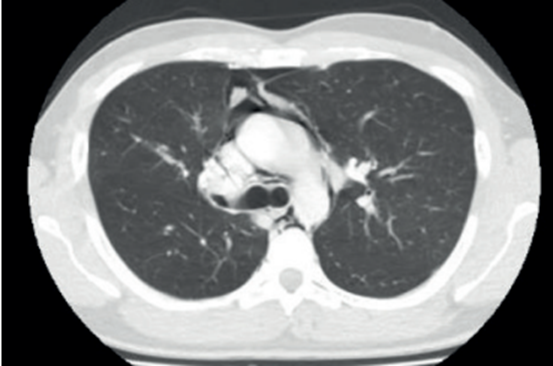

Figura1: En tomografía de tórax se observa extenso neumomediastino que diseca y se extiende a la pared derecha del hemitórax y hacia el cuello.

No se visualizan otras alteraciones parenquimatosas pulmonares (figuras2,3y4).

De la analítica a destacar: glóbulos blancos 16.000/mm3. Desarrolla insuficiencia respiratoria severa, tirajes altos y bajos, saturación de O2 67%, ingresando a unidad de cuidados intensivos. Se procede a intubación orotraqueal (IOT), murmullo alveolar ventilatorio disminuido, sibilancias en ambos tiempos respiratorios. Se conecta a asistencia respiratoria mecánica constatándose patrón de altas resistencias en vía aérea (RVA 35 m H20/l/seg, Pmax 80 cm H20), gasometría arterial con fracción inspirada de O2 de 100% revela insuficiencia respiratoria severa tipo 2, hipoxemia de 100 e hipercapnia de 149 mmhg. Se inicia sedoanalgesia continua (midazolam 1 mg/kg/hora, fentanilo 8 mcg/kg/hora), bloqueantes neuromusculares (atracurio 0,04 mg/kg/hora) por diez días. De forma complementaria dado el bronco espasmo severo y difícil adaptación a asistencia respiratoria mecánica, se recurrió a ketamina (0,3 mg/kg/min) por 72 horas. Se optimizó tratamiento broncodilatador (salbutamol y bromuro ipratropio inhalado de forma reglada) y corticoides sistémicos (hidrocortisona 100 mg cada 8 horas por 7 días), con descenso gradual en días consecutivos, logrando estabilización respiratoria con descenso progresivo de presiones en VA, mejoría progresiva del intercambio de gases. A 48 horas se realiza tomografía de control: disminución del neumomediastino y del enfisema subcutáneo, agrega zonas de enfisema en cara anterior del tórax por delante del manubrio esternal, en regiones maseteras y burbujas aéreas a nivel de espacios faringomucosos, prevertebral y neumorraquis (figuras5y6).